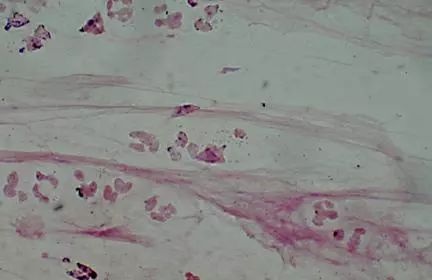

(2)痰液评估

开始抗生素治疗前应进行痰革兰氏染色和培养。革兰氏染色可能会观察到单一的主要微生物,尽管吸痰时厌氧菌污染可能会观察到混合菌群。